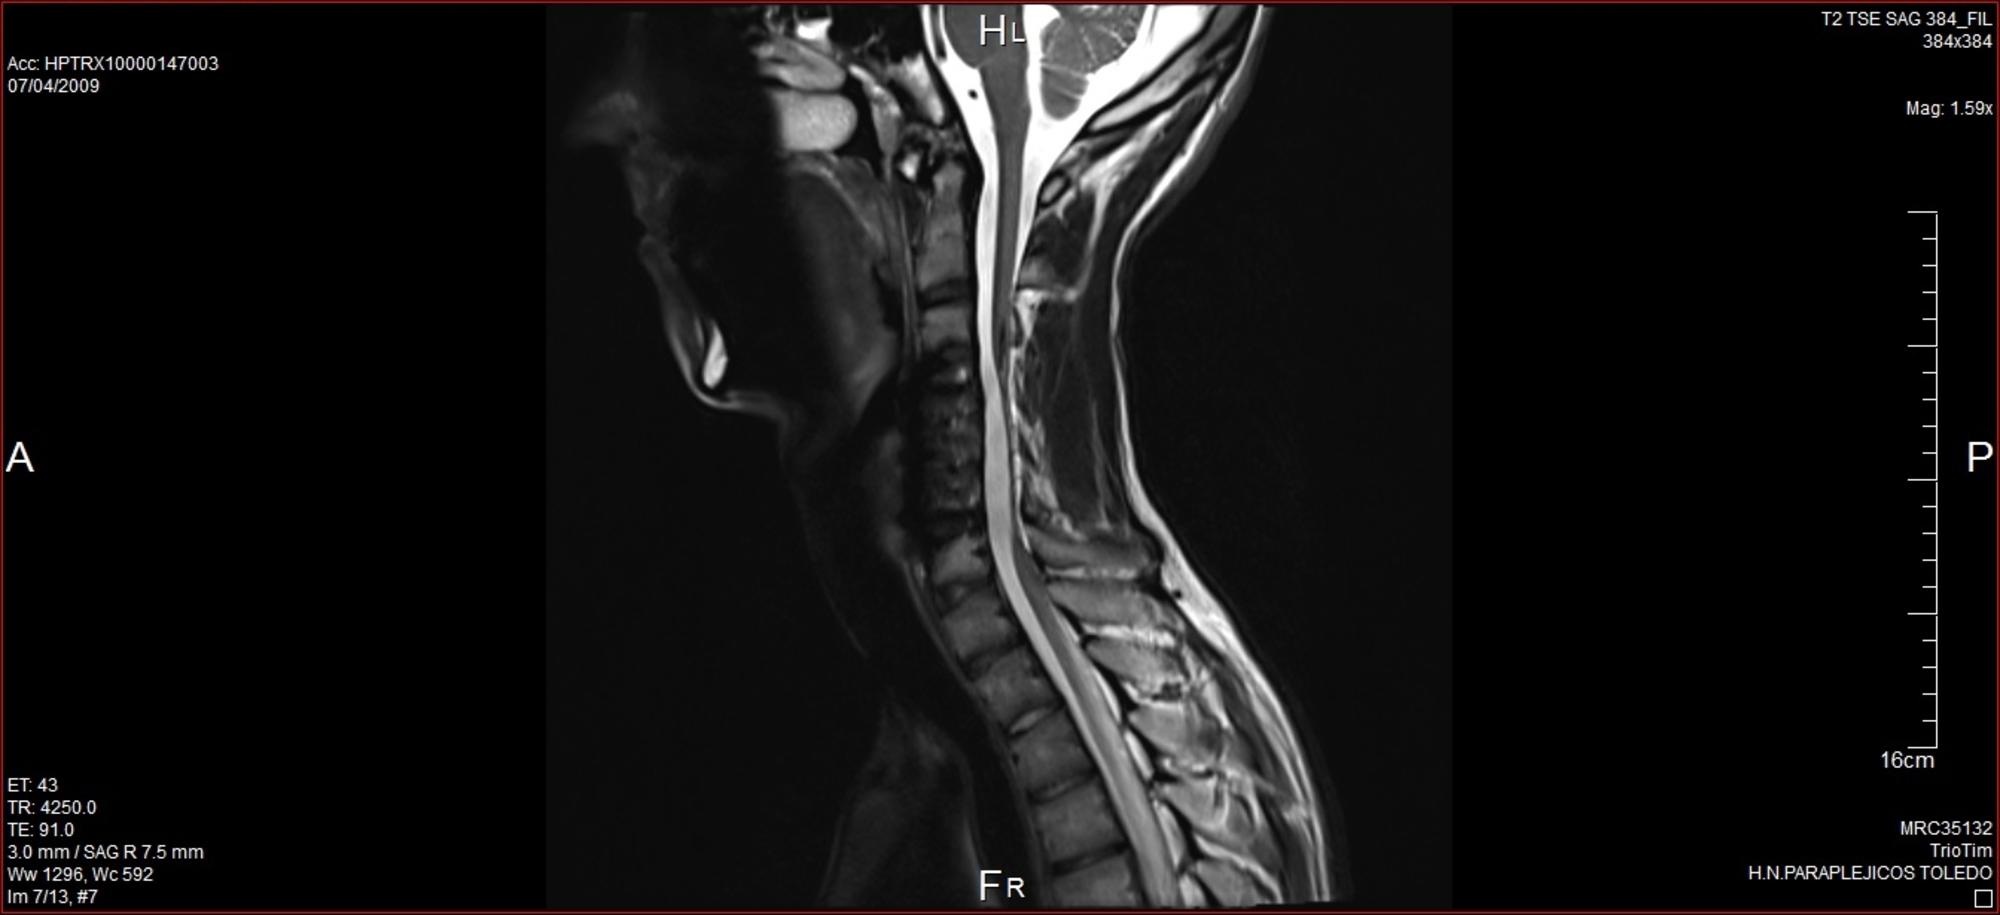

Resonancia Lesión Medular

Resonancia magnética donde se observa la zona donde se produjo la lesión medular. Nerea Gabilondo